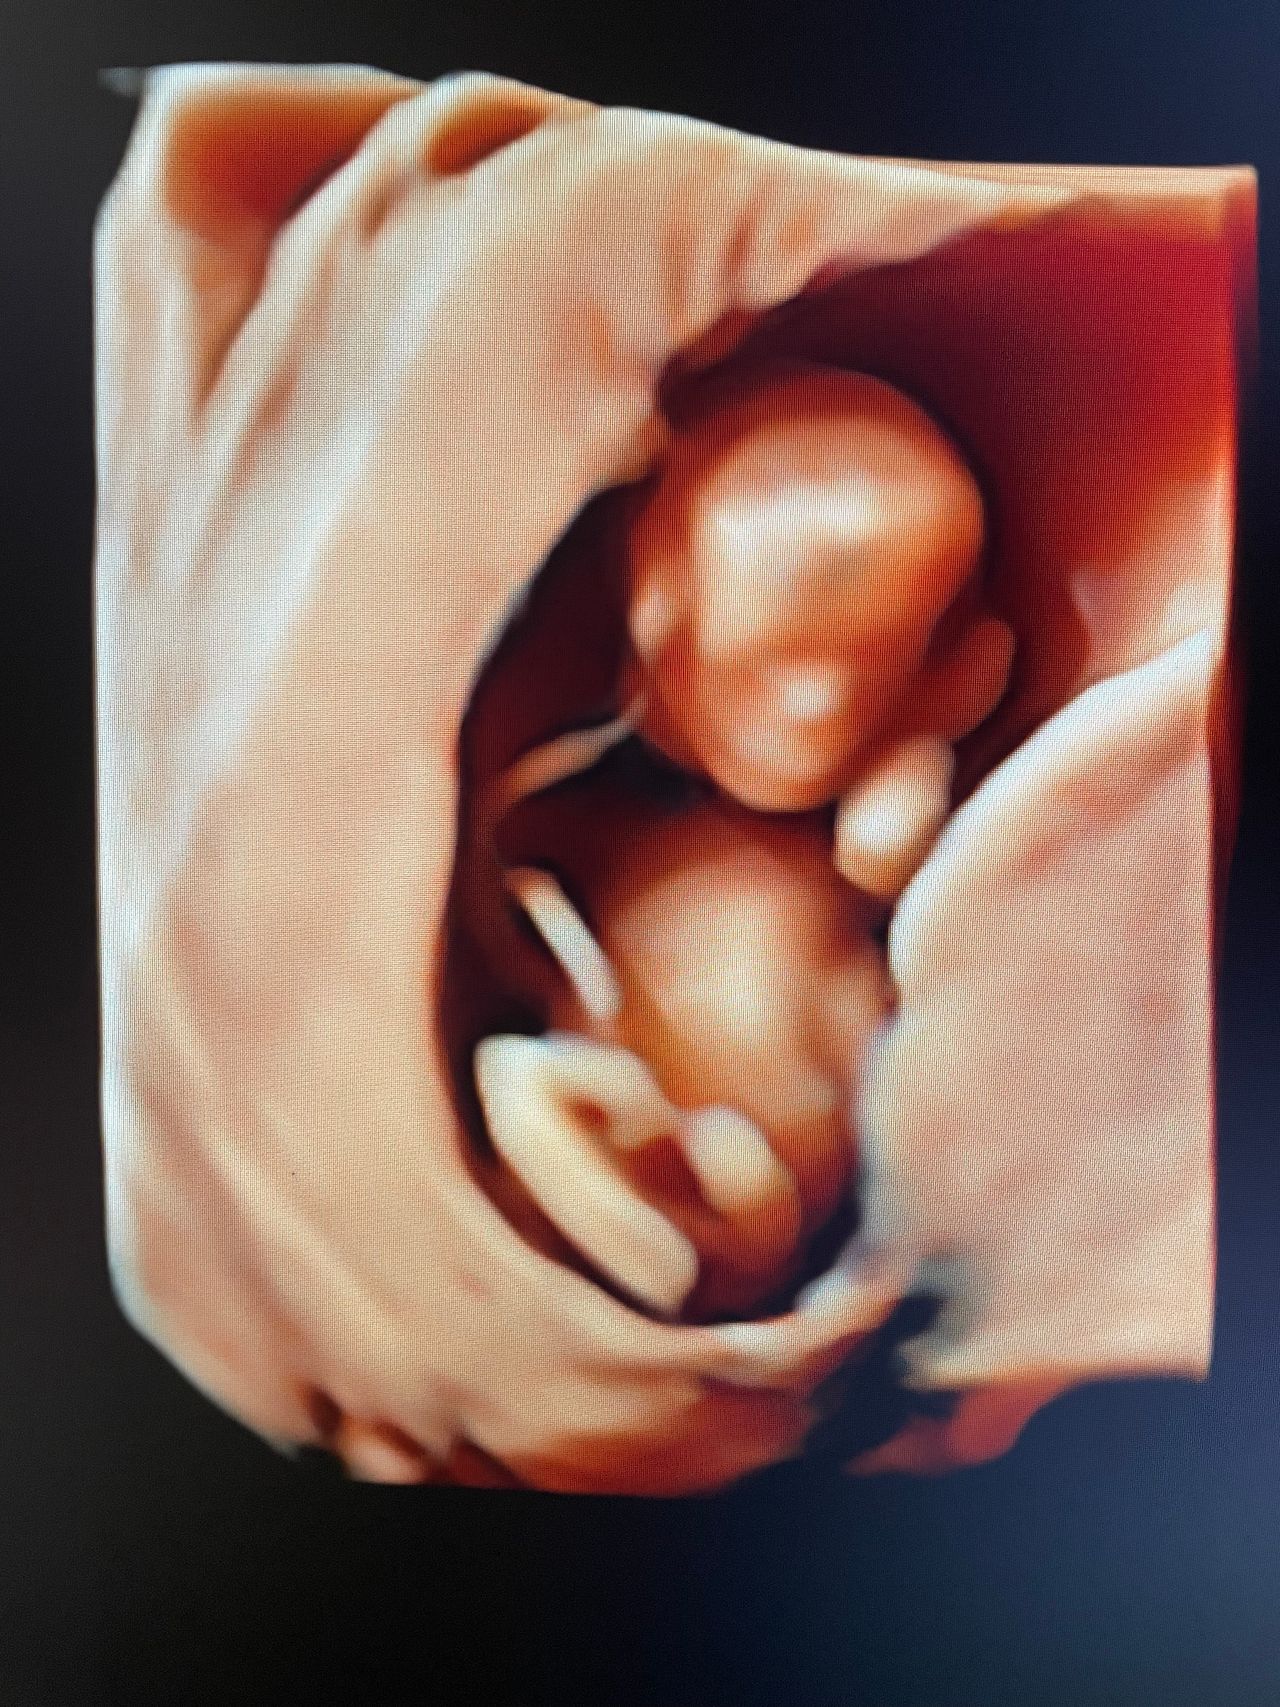

In gravidanza effettuo visite ostetriche, ecografie del I trimestre (datazione e translucenza nucale), calcolo del rischio del I trimestre (Bi test), cervicometria, ecografie del III trimestre (accrescimento e flussimetria fetale) ed ecografie 3D/4D.